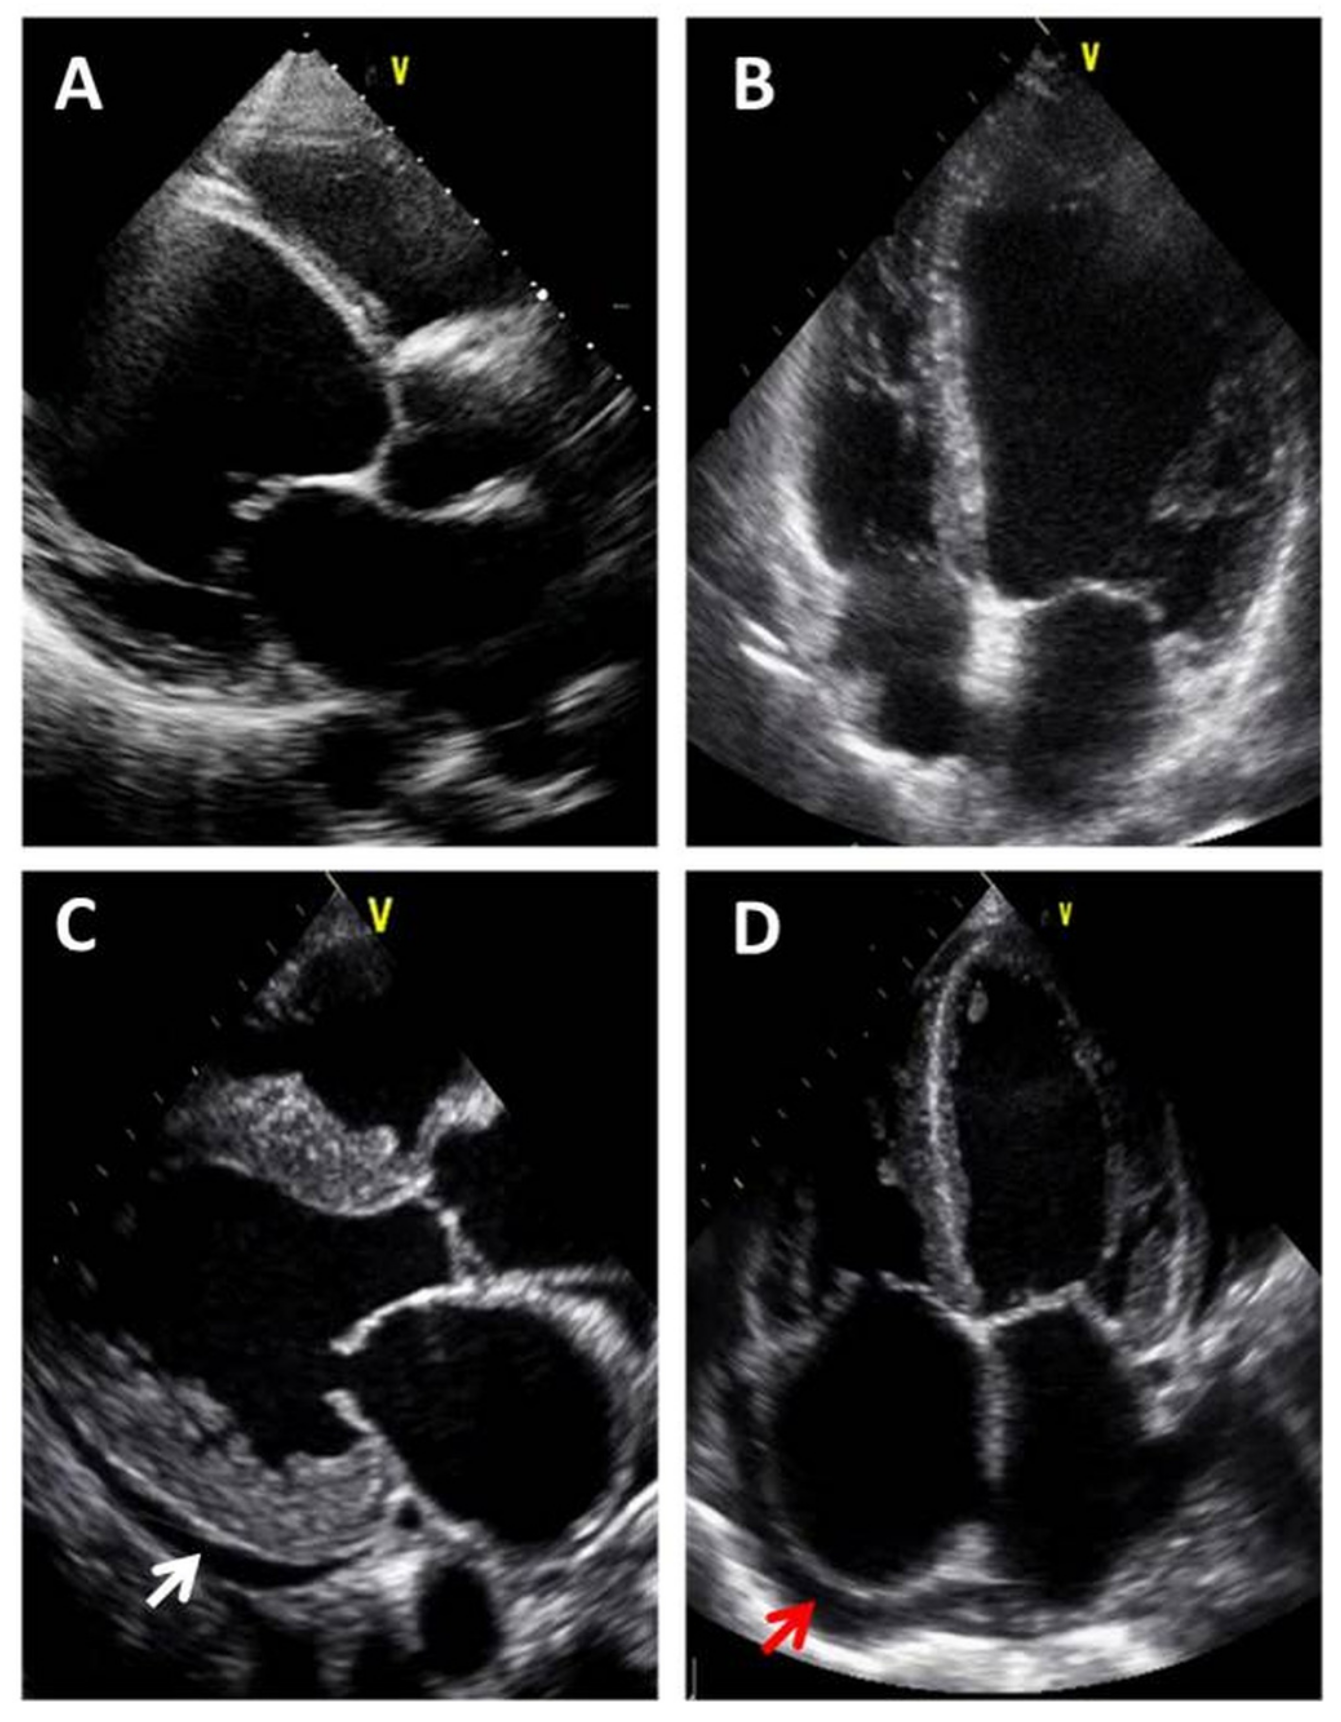

2. Differentiation of the Various Echocardiographic Equipment: From Standard, Comprehensive Transthoracic Echocardiography to Focused Cardiac Ultrasound